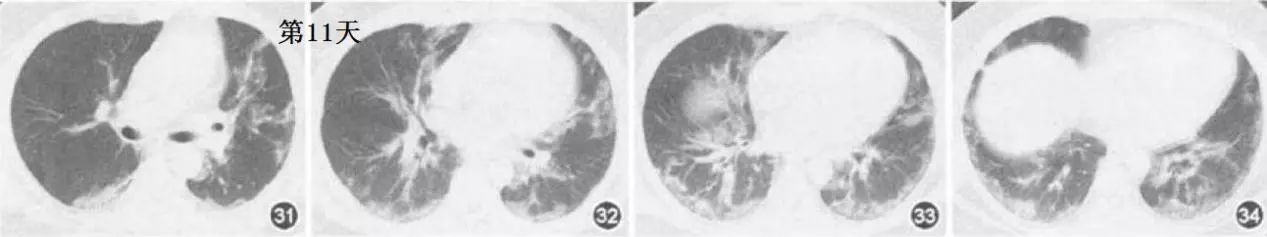

文献3:北京地坛医院放射科,杨钧等报道的一例(甲型H1 N1流感合并肺炎的影像表现)。

双肺多个空洞和气囊影。这个CT一般要考虑金葡菌感染,不像流感肺炎,但是,这个患者是流感后继发金葡菌感染。

文献4:吉林大学第一院报道(甲型H1N1流感合并肺炎的重症及危重症老年患者23例

临床分析)。

这个CT没有什么特殊的地方,这个时候只有结合临床、流行病学综合分析了。